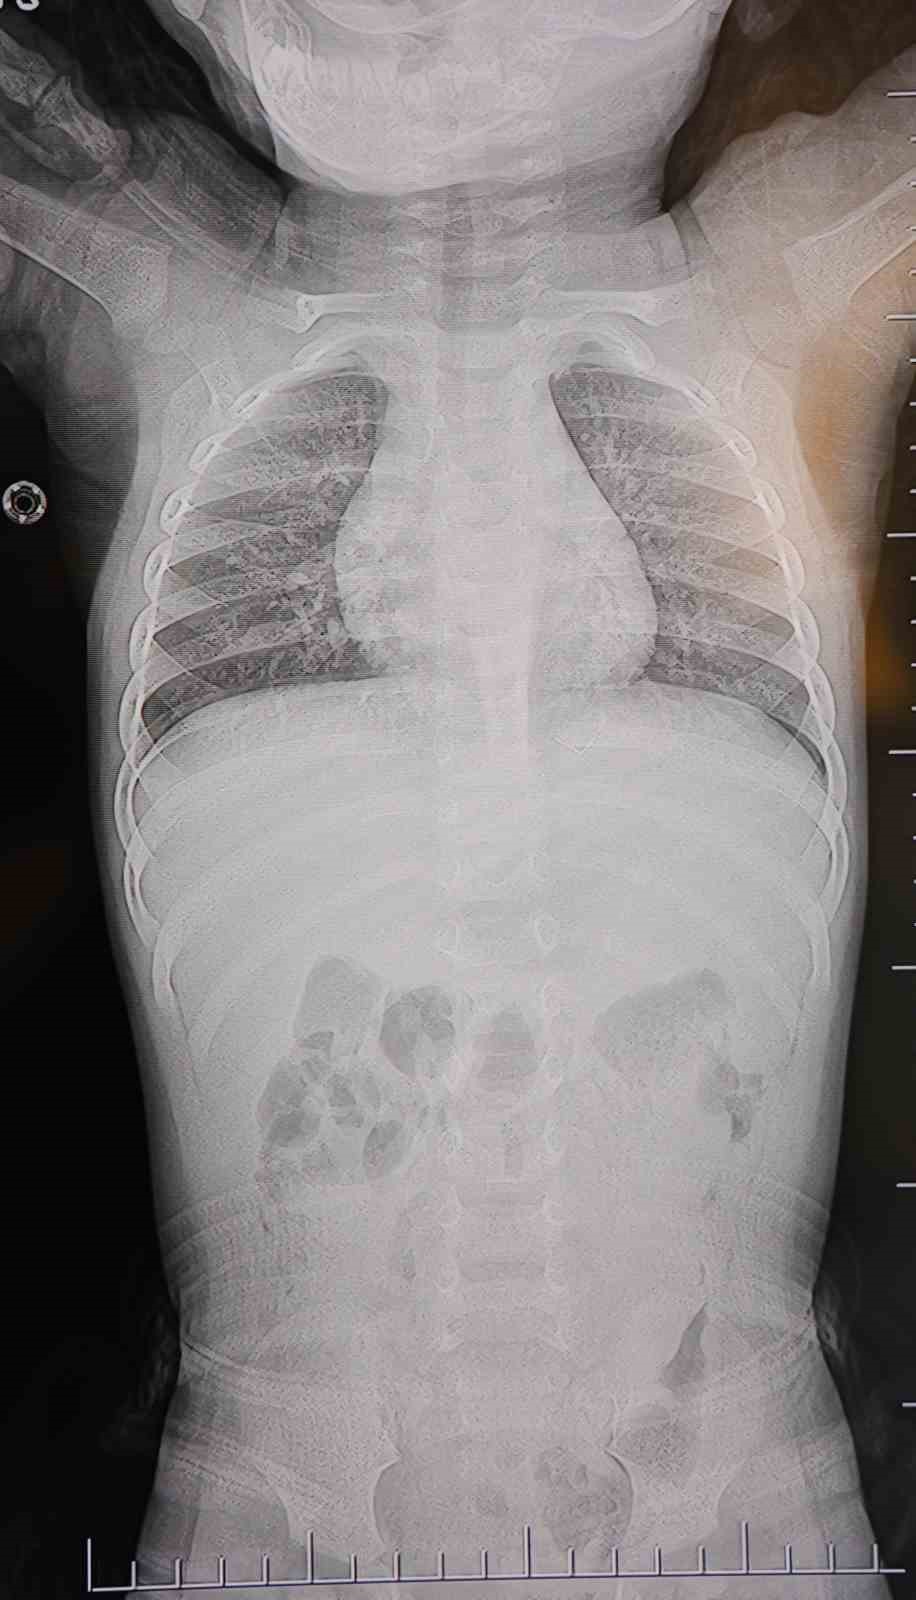

Baba Poyraz, bir gün acil serviste yapılan kontrollerde bebeğin belinde yabancı cisim olduğunu, çekilen filmlerde ise "L" şeklinde zımba teli tespit edildiğini söyledi. Çeşitli hastanelere yönlendirildiklerini anlatan baba, uzun süre müdahale edilmediğini, daha sonra özel bir hastanede yapılan operasyonla zımba telinin çıkarıldığını kaydetti.

Poyraz, bebeğin doğduktan sonra sarılık diyerek kuvöze alındığını belirterek, "Bir hafta orada yattı. Sonra çıkardılar, eve getirdik. Eve geldikten sonra gece gündüz ağlaması hiç durmadı. Tekrar hastaneye götürdüm. Kaşınıyordu, bir hafta banyo yaptıramadık. Sonra duş aldırdım, bağırması daha da arttı. Belini açtık, sırtına baktık, bir şey var mı diye kontrol ettik, görünürde yoktu. Hastaneye götürdük, şurup verdiler. Aylar geçti. Daha sonra acilde bir doktor çocuğumun belinde yabancı cisim olduğunu söyledi. 184’ü aradım, şikayette bulundum. Başhekim yardımcısının yönlendirmesiyle tomografi çekildi. O zaman belinde zımba teli olduğu netleşti. Başka bir hastaneye götürdük, ’riskli, 8 yaşına kadar alınamaz’ dediler, geri gönderdiler. Eve geldikten üç gün sonra oğlum bayıldı. Kardeşimle özel hastaneye götürdük. Orada filmlere baktılar, ’akciğere doğru gidiyor, L şeklinde zımba teli var, alınması lazım’ dediler" dedi.